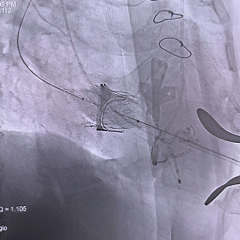

术中影像

瓣膜重新释放至全展开位,可见位置合适,流出端可见形态压缩

超声评估瓣膜位置可,无瓣周漏

28mm球囊后扩,瓣膜形态明显改善

最终评估可见瓣膜形态、位置均理想